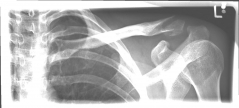

Picture 1                                                                Picture 2

Picture 2: After the operation, the fracture is correctly repositioned and held in position with a titanium plate and two screws..